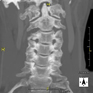

- Cervical spine CT

Radiological test that provides high definition anatomical images of the cervical vertebrae using CT (Computed Tomography) equipment. Indicated for: cervical pain without/with irradiation to the arms, trauma.